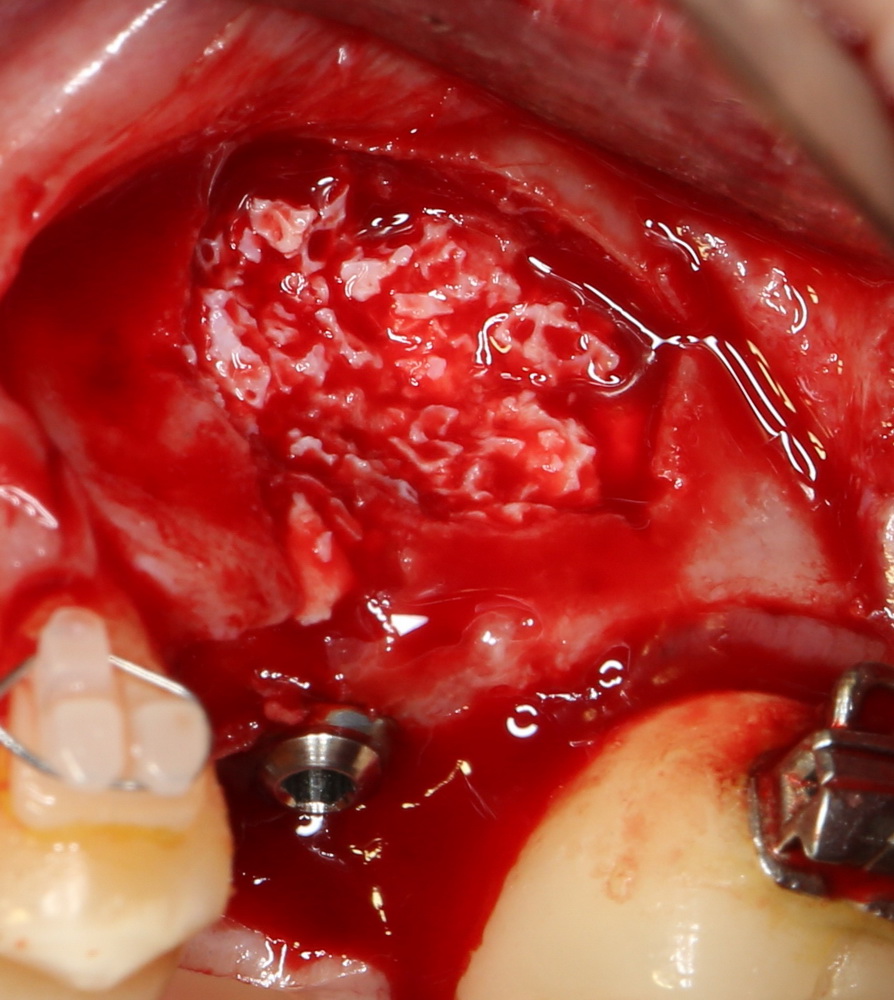

Синуслифтинг и имплантация

Конечная цель операции синуслифтинга – создание адекватных условий для установки имплантов. При этом, нередко удается провести имплантацию одновременно с операцией синуслифтинга. Как уже говорилось выше, это возможно, если существующий объем костной ткани позволяет стабилизировать имплантат заданного размера (рис 43, 44, 45):

Рисунок 43, 44, 45. Установка имплантов одномоментно с операцией синуслифтинга: слева – этап синуслифтинга, в центре – подготовка лунки под имплантат (виден спейсер и слизистая оболочка гайморовой пазухи), справа – установленный имплант

Оптимальное расстояние от дна гайморовой пазухи до верхней точки альвеолярного гребня верхней челюсти, при котором возможна стабилизация импланта длиной 10-11 мм – не менее 3-4 мм. Однако, в некоторых случаях имплантат длиной 11 мм удается стабилизировать в меньшем объеме костной ткани (рис 46, 47, 48):